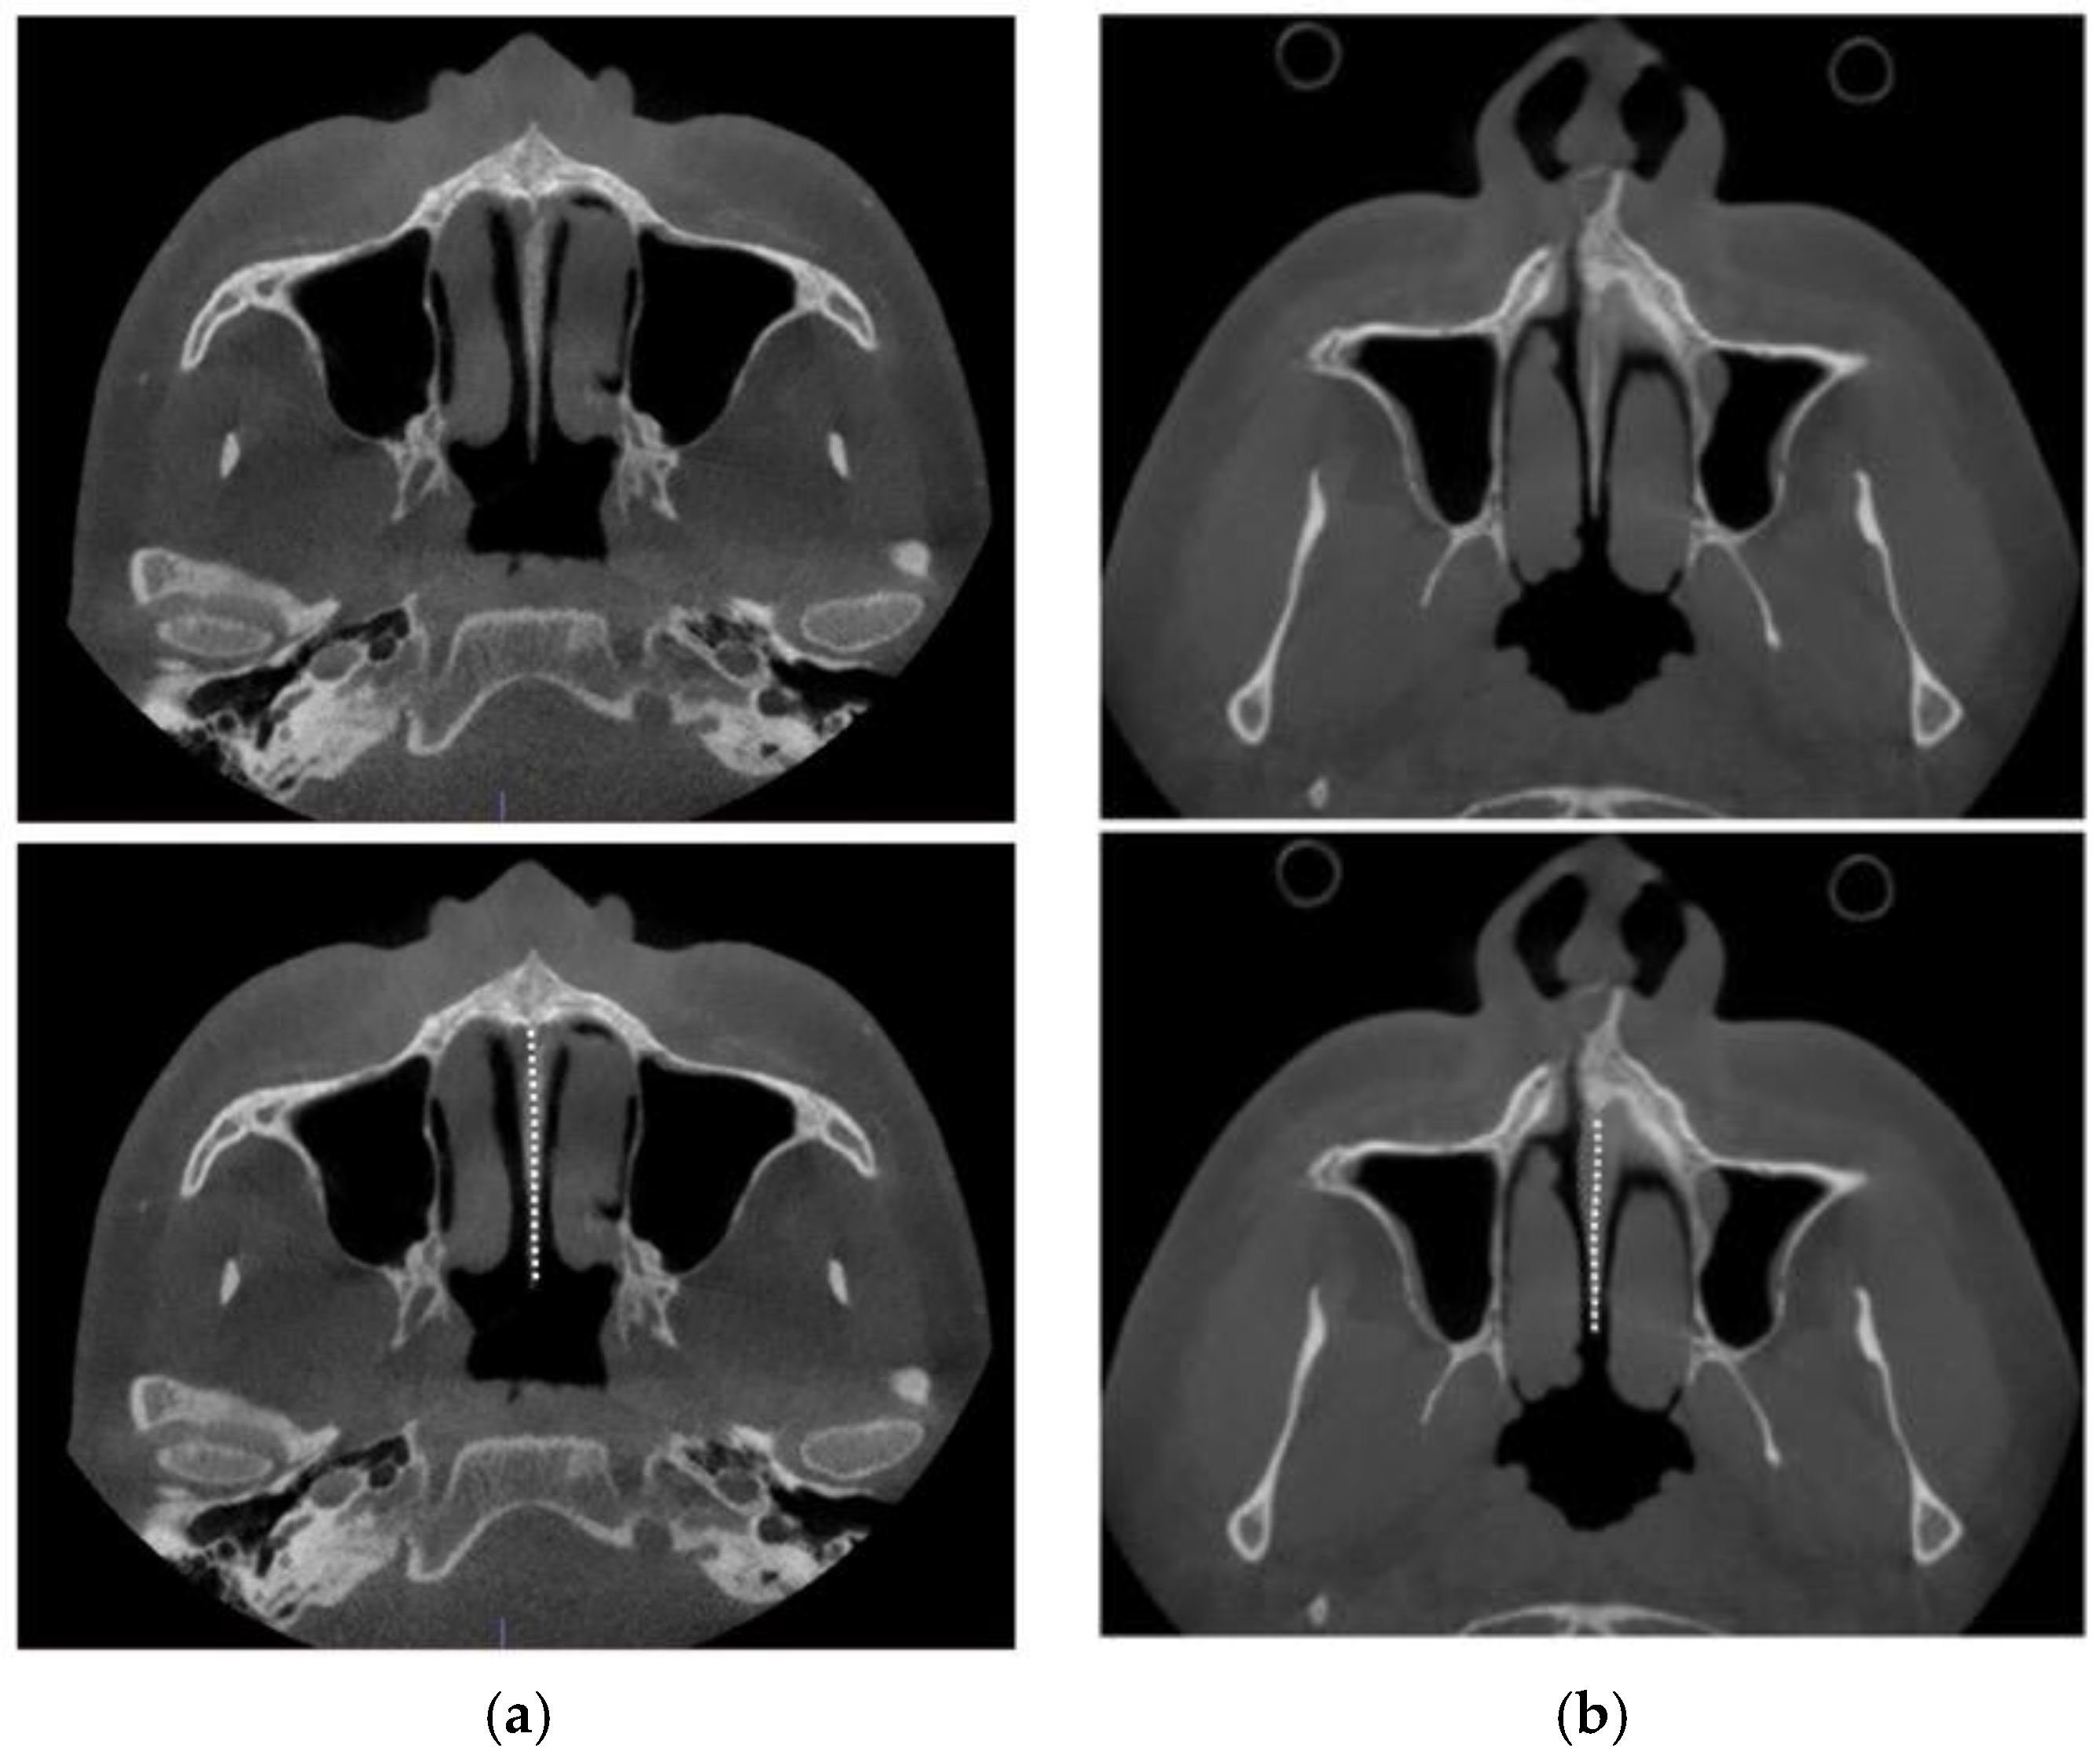

2.4. Case A: Blind Midpalatal Piezocorticotomy with MARPE Expansion

2.5. Case B: Guide-Assisted Midpalatal Piezocorticotomy